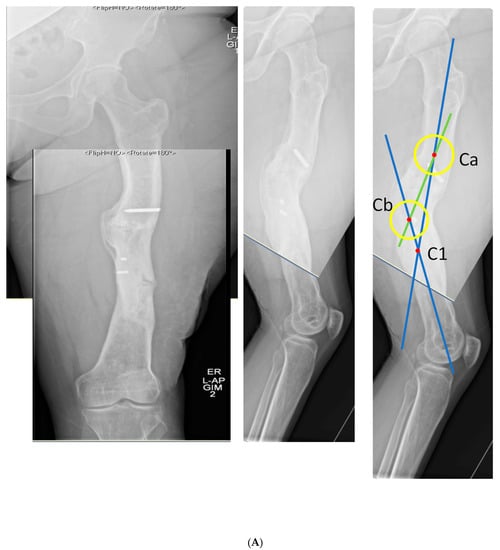

Figure 6.

(A) Middle-aged female with 26 years of an infected draining sinus of the left femur with malunion and shortening. The intersection of the two blue lines represents the CORA of the proximal and distal diaphyseal segments (C1). A CORA outside of the deformity reveals translation in addition to angulation. The intersection of the green line with each blue line represents an alternative where the central deformed segment is also incorporated into the analysis, revealing two CORA center points for double-level osteotomy (Ca and Cb). (B) The patient was found to have retained hardware and a bone sequestrum. Sequestrectomy with antibiotic local delivery via a coated intramedullary nail with concomitant systemic antibiotics would promote infection eradication. (C) The patient underwent double-level focal dome osteotomy at the time of initial debridement. The patient had two sequential debridements over 10 days. Stabilization using an interlocking antibiotic coated nail was placed during the final debridement. (D) Five months postoperative, where the distal osteotomy was autogenous-grafted from the patient’s contralateral femur due to the persistent osteotomy gap. Chronic suppression oral antibiotics were recommended; patient voluntarily stopped antibiotics at 24 months. (E) Three-year final follow-up with normal serological markers and no sign of recurrence. Osteotomies healed. Soft tissue healed.

The patient underwent double osteotomy using focal dome osteotomy at Ca and Cb (Figure 6C), with retained hardware removal and resection of the infected sequestrum and surrounding diseased bone. A direct lateral approach to the thigh was used, and the diseased soft tissue track was excised and analyzed by pathology. A temporary nail was inserted and replaced with an antibiotic-coated interlocking nail ten days later with a planned second debridement. The nail was compressed using the internal compression instrumentation associated with the nail. A gap in the distal osteotomy persisted despite attempted removal of the nail and re-reaming with enlarging flexible reamers. This gap was accepted with intent to revisit if bone healing did not progress. The surgical soft tissue approach healed without incident. At five months postoperative, with nonunion of the distal osteotomy at the gap, the patient underwent autograft using contralateral femur reamer–irrigator–aspirator harvesting (Figure 6D). Cultures at the grafting procedure were negative.

The patient progressed to pain-free union at both osteotomies with no recurrence of her infection over three years after osteotomy (Figure 6E).